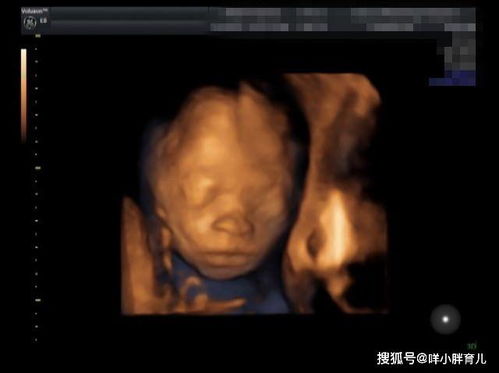

孕妇被宝宝四维彩超丑哭:真相与反思 本文讲述了孕妇通过四维彩超看到宝宝长相后感到失望的真实故事,深入探讨了四维彩超的意义以及AI预测宝宝长相的现象,呼吁准父母正确看待这些问题。 头条热点 2025年01月19日 20:47 0 点赞 0 评论 56 浏览